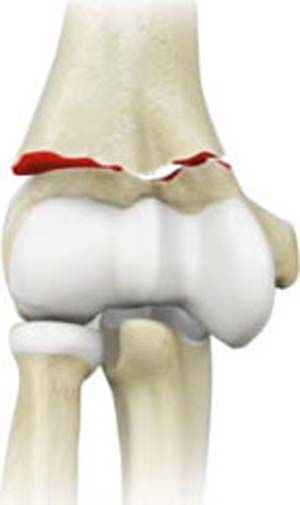

Elbow Fractures

Fractures of the Hand and Fingers